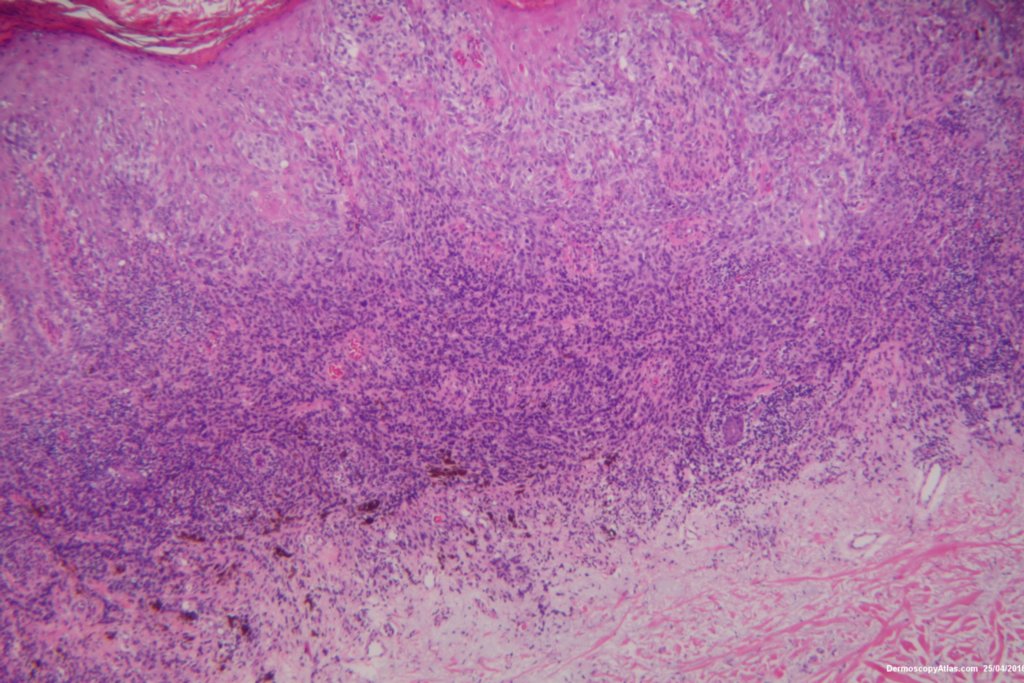

Image Number #3392 (Melanoma invasive)

Diagnosis: Melanoma invasive

Description: Lesion on the thigh

This 57 years old male presented with a lesion on his thigh that he said had only been present for 6 weeks. It looked and felt keratotic and had a bluish discolouration associated with it. It was thought to be an irritated Seborrhoeic keratosis perhaps with some bleeding into it to account for the blue colour.

The shave biopsy was reported as a level 4 Invasive melanoma 1.7 mm thick with 3 mitoses per high powered field. There were no groin glands enlarged clinically.